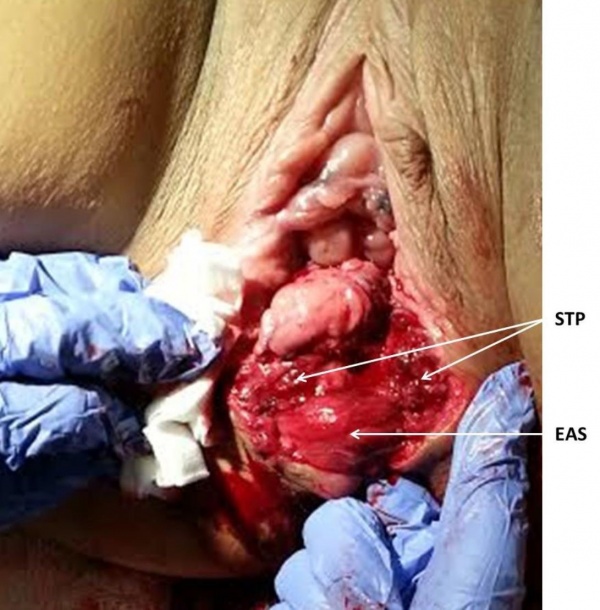

- יש לתקן את הסוגרים בהתאם לדרגת הקרע. רצוי לבודד ולזהות כל שכבה בנפרד (ראו נספח).

נספח - המלצות לתפירת הקרע[1]

- קרעים דרגה 4 המערבים את רירית פי הטבעת, רצוי לתפור את הרירית בתפרי (Vicryl (polyglactin 3-0 בודדים. אין חשיבות אם הקשר פונה לתעלה האנאלית או לצד הנגדי. מומלץ להימנע מתפרים כפולים (8 figure of) כיוון שיכולים לגרום לאיסכמיה של הרירית

- קרעים של סוגר פי הטבעת הפנימי (קרע דרגה 3c) רצוי לתקן את הסוגר הפנימי בנפרד ב־2-3 תפרי0–3 PDS או בתפרי 0–2 (Vicryl (polyglactin בשיטת U (דומה לשיטת end-to-end של הסוגר החיצון)

- קרעים של הסוגר החיצוני ניתן לתקן בשתי שיטות: End to end ו- Overlap